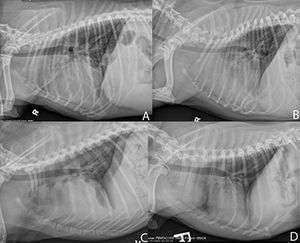

Thymoma in an 11-year-old dog: Radiology perspectiveByAdrien Hespel, DVM, MS, DACVRMay 31st 2019Dr. Adrien Hespel provides the radiology perspective on this thymoma case.